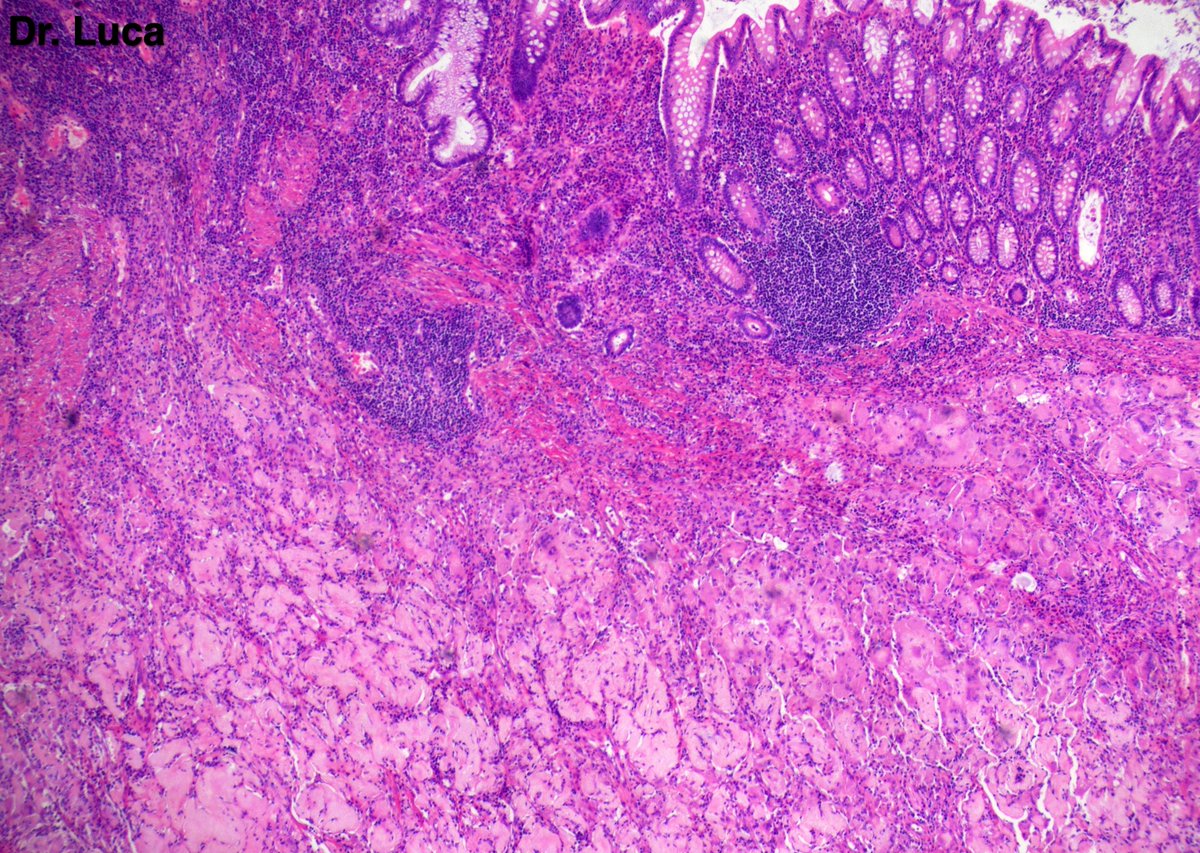

@Pathmath1 @SumantaDas_7 @PoloniaAntonio @ivanaspath @AnapathResident @bansar7 @goziemnweke @Teclis82 @Dr_Brian_Cox @DrBMcGinn @ariella8 @nusrat_xahra @DrRusella_Mirza @glinglerimek @kis_lorand @Venkateshgilly2 @DrBonita16 @DrPayelMondal @DrGeeONE @anjuthevirgo @niki_2389 @pepeheffernan @AngeloCassisa @NeoCrazee @TristanRutland7 Yes, it's a cancer with PNI...I show you the "superficial" layer of this cancer...what is the cancer? and what is the organ? #Pathology #GIpath #PathTwitter #PathResidents #pathboards